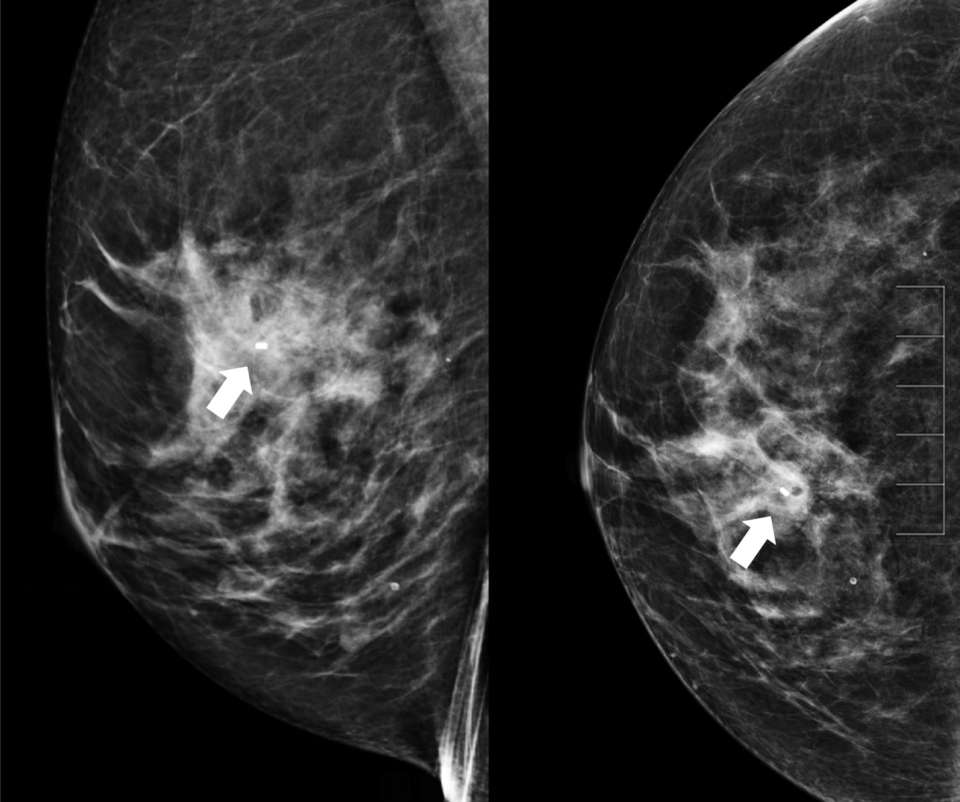

• Technologist takes 2D or 3D mammograms in CC and ML views (Figure 7).

• Radiologist evaluates for adequate biopsy marker placement.

How to perform: Sterotactic (Mammographic guided biopsy) Figure 7

Figure 7. Post-procedure ML (left) and CC (right) images demonstrate good biopsy marker placement (arrow).